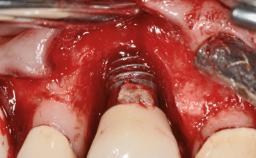

Repeated Acrylic Fractures on a Mandibular Fixed Full-arch Implant-supported Metal/Acrylic Prosthesis

A 77-year-old male patient was referred for the management of frequent and repeated acrylic fracture of his existing mandibular fixed full-arch implant-supported metal/acrylic prosthesis. He also complained about softtissue soreness and the lack of retention and stability of his maxillary removable partial metal/acrylic prosthesis. Both prostheses had been delivered two years previously as part of his full-mouth rehabilitation (caries, tooth wear, tooth fracture). His medical history revealed high blood pressure, controlled with the use of antihypertensive medication.

Defining Characteristics Fully edentulous lower jaw to be rehabilitated with two or more implants

Modality > 4 implants, extending to mental nerve region